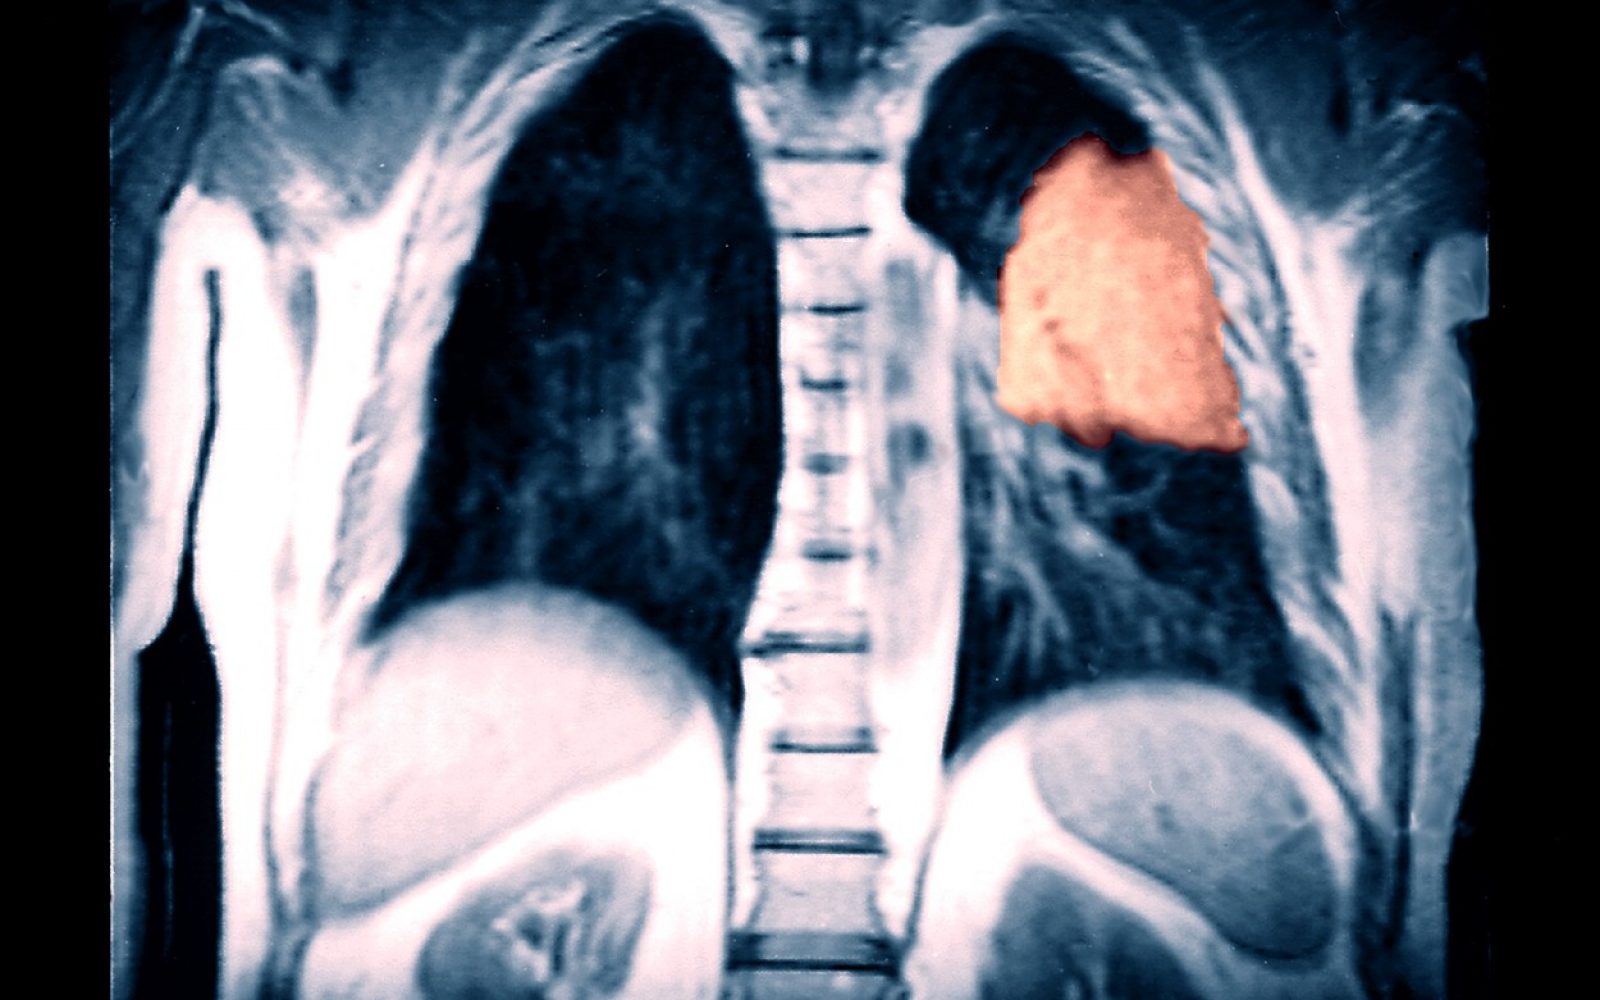

V Sloveniji letno diagnosticirajo okoli 1500 bolnikov z rakom pljuč, od tega okoli 40 odstotkov na Kliniki Golnik. “Umrljivost je še naprej dokaj visoka. Vsako leto zaradi te bolezni umre okoli 1200 bolnikov in tu imamo še velike možnosti izboljšave,” je prepričana Janžičeva.

Podatki kažejo, da je več kot polovica bolezni odkritih v napredovalnem metastatskem stadiju, ko ni več ozdravljiva. “Ta odstotek se na srečo nekoliko zmanjšuje, tako da lahko več bolnikov ozdravimo,” je povedala Janžičeva.

Zbrani podatki kažejo, da je bilo petletno preživetje pri bolnikih, pri katerih je bil rak ugotovljen v prvem stadiju, od 60- do 70-odstoten. Pri tem zelo pomembno vlogo igrajo operacije, ki jih na Golniku izvaja Kirurgija Bitenc, kjer so v tem času izvedli okoli 1250 operacij. Pri tistih, ki je bolezen že toliko napredovala, da so se že razvile metastaze in so bili napoteni samo na sistemsko terapijo, pa je povprečno preživetje znašalo le eno leto.